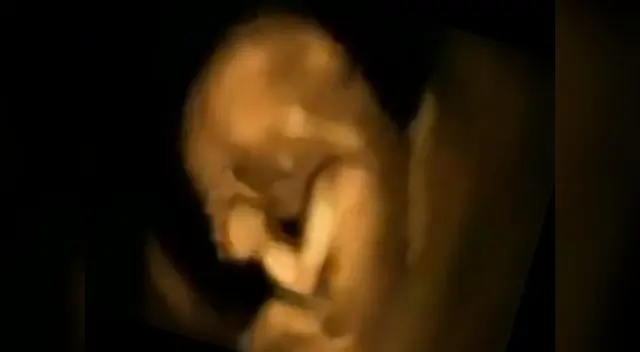

Los padres fueron por primera vez a ver a su hijo que crece en el vientre de su madre, y gracias a la ecografía 4D los progenitores pueden ver directamente cómo será el futuro de su bebé y su estado en la gestación.

El vídeo publicado en la página de Facebook de Meddy Bear, nos presentó a un feto en estado de gestación, estaba muy inquieto, incluso parece que baila. Debido a los movimientos tan bruscos, sorprendió a los médicos quienes indicaron a la familia que se trataría de un bebé muy sano.

“Eso es exactamente lo que siento que debe estar pasando en mi vientre, pero es muy bonito poder verlo, porque es algo que no puedo hacer.”, comentan usuarias emocionadas, en el post de Facebook que actualmente cuenta con más de 230 mil compartidos y miles de comentarios de madres que agradecen este milagro de vida.